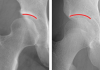

[제주, 제주인의 건강보고서 Ⅷ 건강다이어리] (160)고관절 이형성증

타고난 관절 구조가 원인특히 여성에게 자주 발병퇴행성 관절염으로 이어져조기 진단·맞…